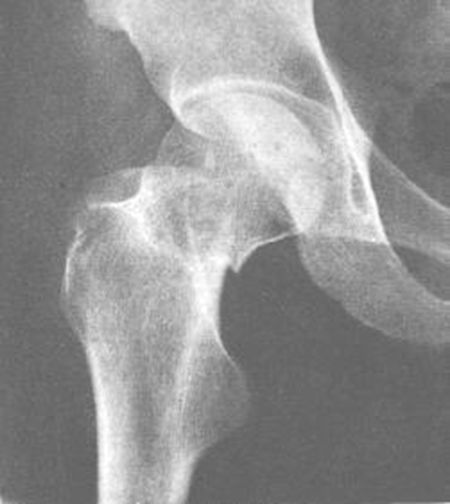

髋关节后脱位

髋关节前脱位